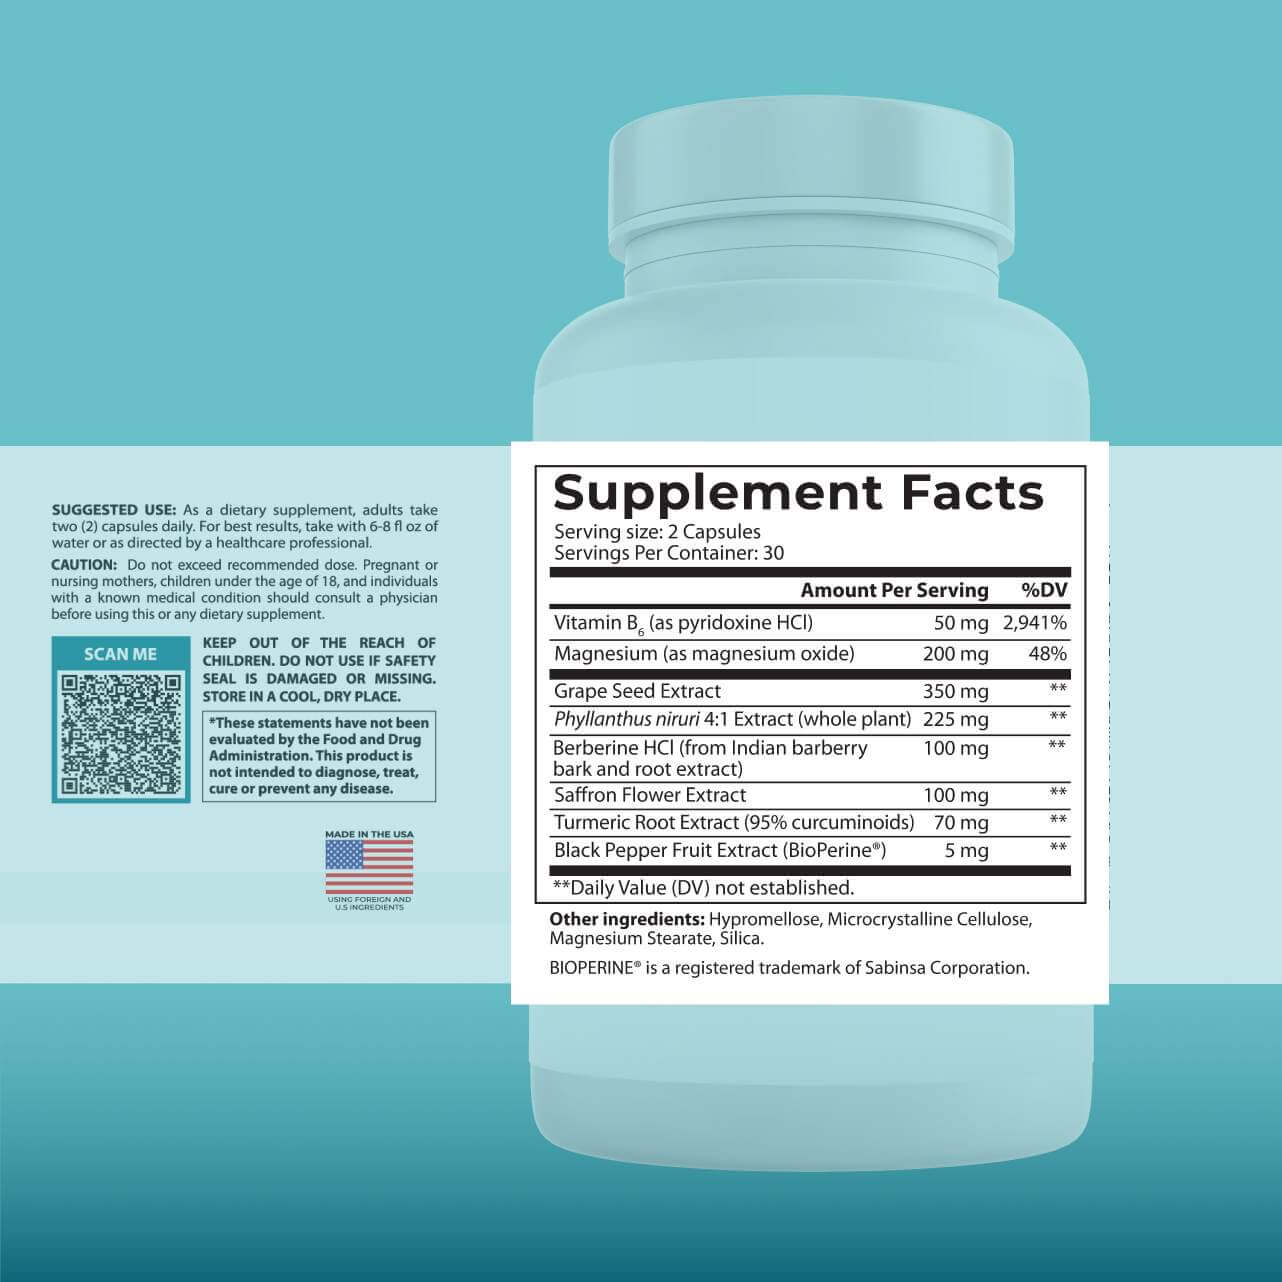

HOW DO YOU USE KIDNEY HEALTH FORMULA?

SUGGESTED USE: As a dietary supplement, take two (2) capsules daily, with a meal and 8 fl oz of water, or as directed by a healthcare professional. Keep out of the reach of children. Do NOT use it if safety seal is damaged or missing. Store in a cool, dry place.

WHAT ARE THE EFFECTIVE INGREDIENTS IN KIDNEY HEALTH FORMULA?

Vitamin B6: Clinically proven to have potential for lowering urine oxalate excretion—the most common cause of kidney stones. In a groundbreaking study of 95 patients with elevated oxalate levels, 75% showed significant decrease in urinary oxalate excretion, and 39% returned to normal range after treatment.

Magnesium: A critical mineral for kidney health, associated with improved survival among serious kidney conditions. This specific form—magnesium oxide—could protect against arterial hardening and has shown better kidney outcomes than other magnesium forms.

Grape Seed Extract: A powerful antioxidant complex showing remarkable results in clinical trials. In a 6-month study with 23 chronic kidney patients (stages 2-4), GSE demonstrated significant benefits for kidney function, antioxidant status, and reduced protein levels in urine when combined with standard medication.

Chanca Piedra Extract: Known as the "stonebreaker" for its remarkable ability to inhibit kidney stone formation from oxalate and calcium deposits. In a 12-week study with 56 kidney stone patients, this extract normalized uric acid and oxalate levels, reducing stones in 67.8% of participants.

Berberine HCl: A comprehensive kidney supporter that could help maintain healthy blood sugar, cholesterol, and defend against pro-inflammatory activity, and oxidative stress. In a 24-month study with 69 hypertensive patients, berberine significantly improved kidney damage markers, renal blood flow, and protected against toxicity.

Saffron Flower Extract: More than just a culinary spice, saffron shows powerful kidney-protective properties. Demonstrated in 25 preclinical studies to guard against kidney-toxic drugs and toxins. A 12-week study with 80 patients showed significant improvements in systolic numbers and renal function.

Turmeric Root Extract: A renowned kidney superstar that could modulate pro-inflammatory activity and oxidative stress. Clinical studies with 40 patients showed significant reduction in urinary protein excretion. Another 3-month trial with 24 patients demonstrated decreased blood in urine and improved blood pressure.

Black Pepper Extract: A critical absorption optimizer that could dramatically increase turmeric's bioavailability, maximizing its kidney-protective benefits. This patented form ensures optimal absorption of key nutrients.